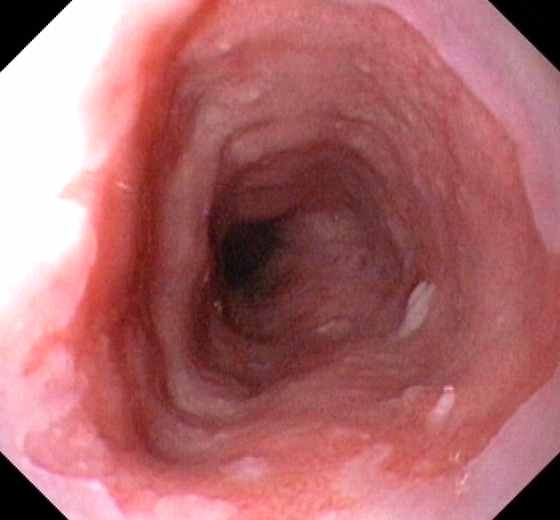

مصرف مادهی مخدر تریاک در ایجاد سرطان معده نقش داشته و همچنین از دیگر سرطانهایی که مصرف تریاک عامل آن است میتوان به سرطان حنجره اشاره کرد.